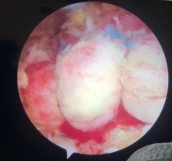

- Vị trí của các mũi khâu, đặc biệt là vị trí ra chỉ của mũi khâu thẳng đứng sao cho hợp với gốc neo chỉ tạo thành một đường thẳng có hướng đi qua hoặc gần nhất với điểm hội tụ CX có thể. Điều này sẽ đảm bảo hướng và lực kéo của gân cơ sẽ đồng nhất với đặc điểm của gân trước rách nhất.

Hình 2.25. Hình vẽ minh hoạ mối liên quan hướng lực kéo gân và điểm hội tụ chóp xoay

* Nguồn: Ảnh vẽ minh hoạ của nhóm nghiên cứu